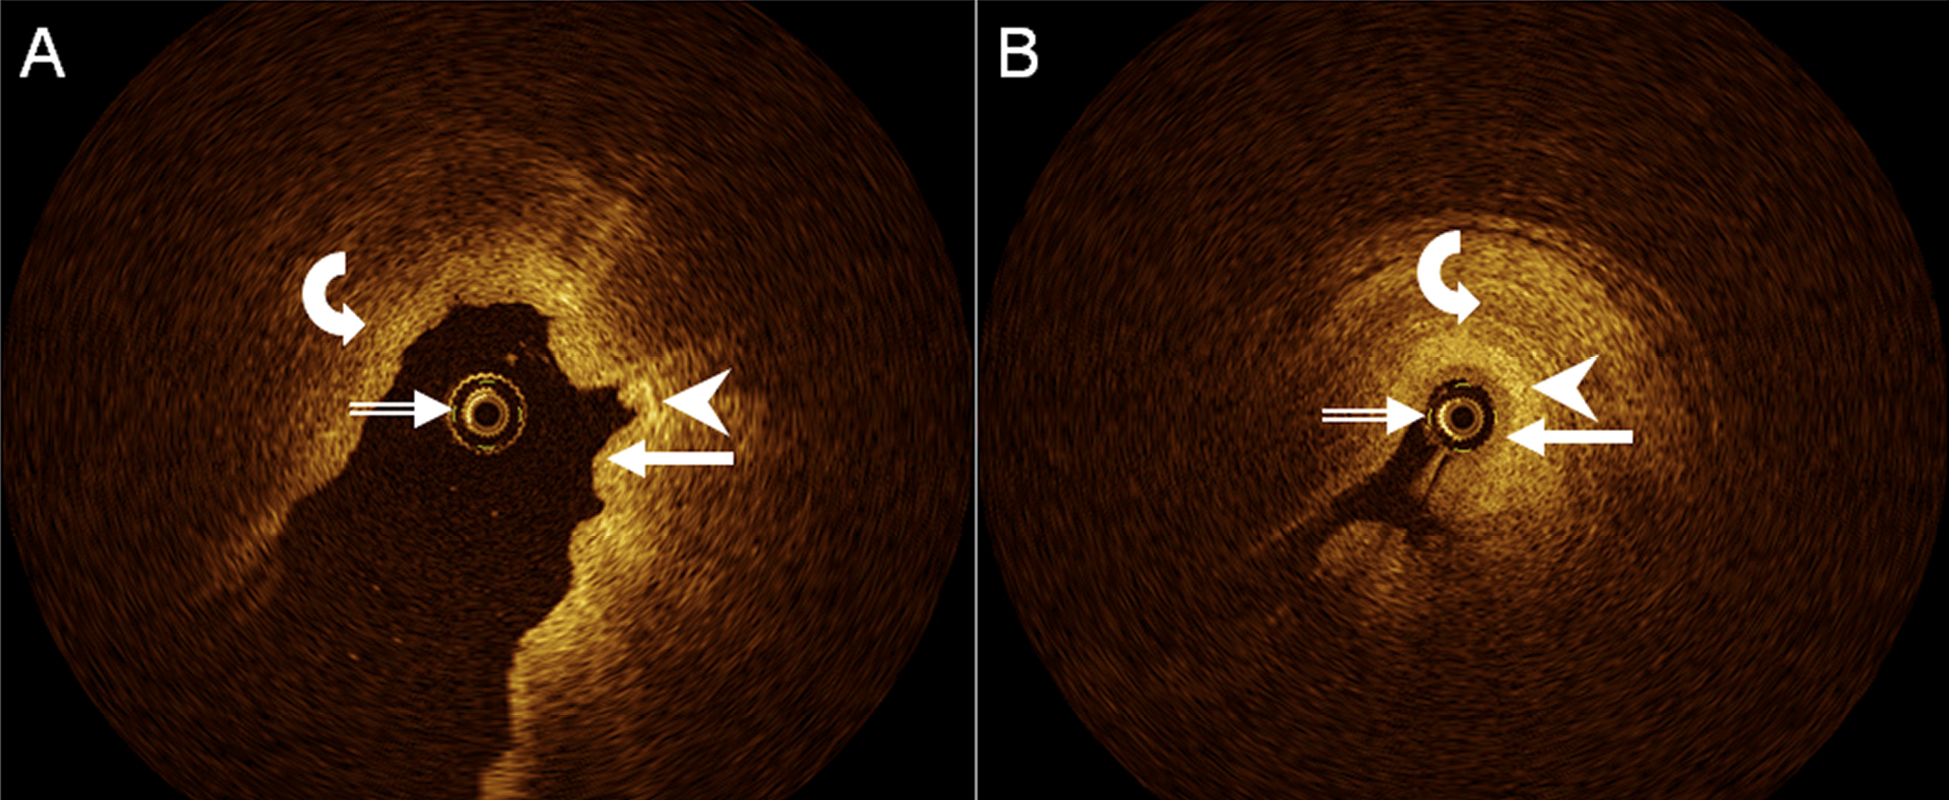

Figure 2. Axial, cross-sectional OCT images of human upper ureter in vivo, A, with fluid distending the ureter lumen, and B, with little fluid within the ureter lumen, demonstrate OCT probe (double-lined white arrows), urothelium (arrows), lamina propria (arrowheads), and muscle layer (curved arrows). Distinct layering of ureter wall appears to be better appreciated in (B).

In all, 532 OCT samples were obtained in 12 different human ureters in vivo, with a range of 20 to 160 samples per patient. In detail, any UUT wall layers delineated in 454 samples (85%; inter-patient range, 68–100%), urothelium and lamina propria, i.e., the first and second layer visualized from inside the ureter lumen, in 362 samples (68%; inter-patient range, 50–96%), and lamina propria and muscle layer i.e., the second and third layer, and moderate for urothelium and lamina propria, in 445 samples (84%; inter-patient range, 61–100%; Fig. 2). Delineation of different UUT muscle layers was modest (191 samples, 36%), with a very wide inter-patient range (5–89%). Delineation of different urothelial cell layers was poor (17 samples, 3%; inter-patient range, 0–14%).

However, there was a wide range between individual patients in the respective proportions of delineations, which did not appear to depend on patient age, gender, or mode of endoscopic access, but may have been related to individual filling state of the UUT lumen and respective distance of the OCT probe from the UUT wall, at least in some instances (Fig. 2).